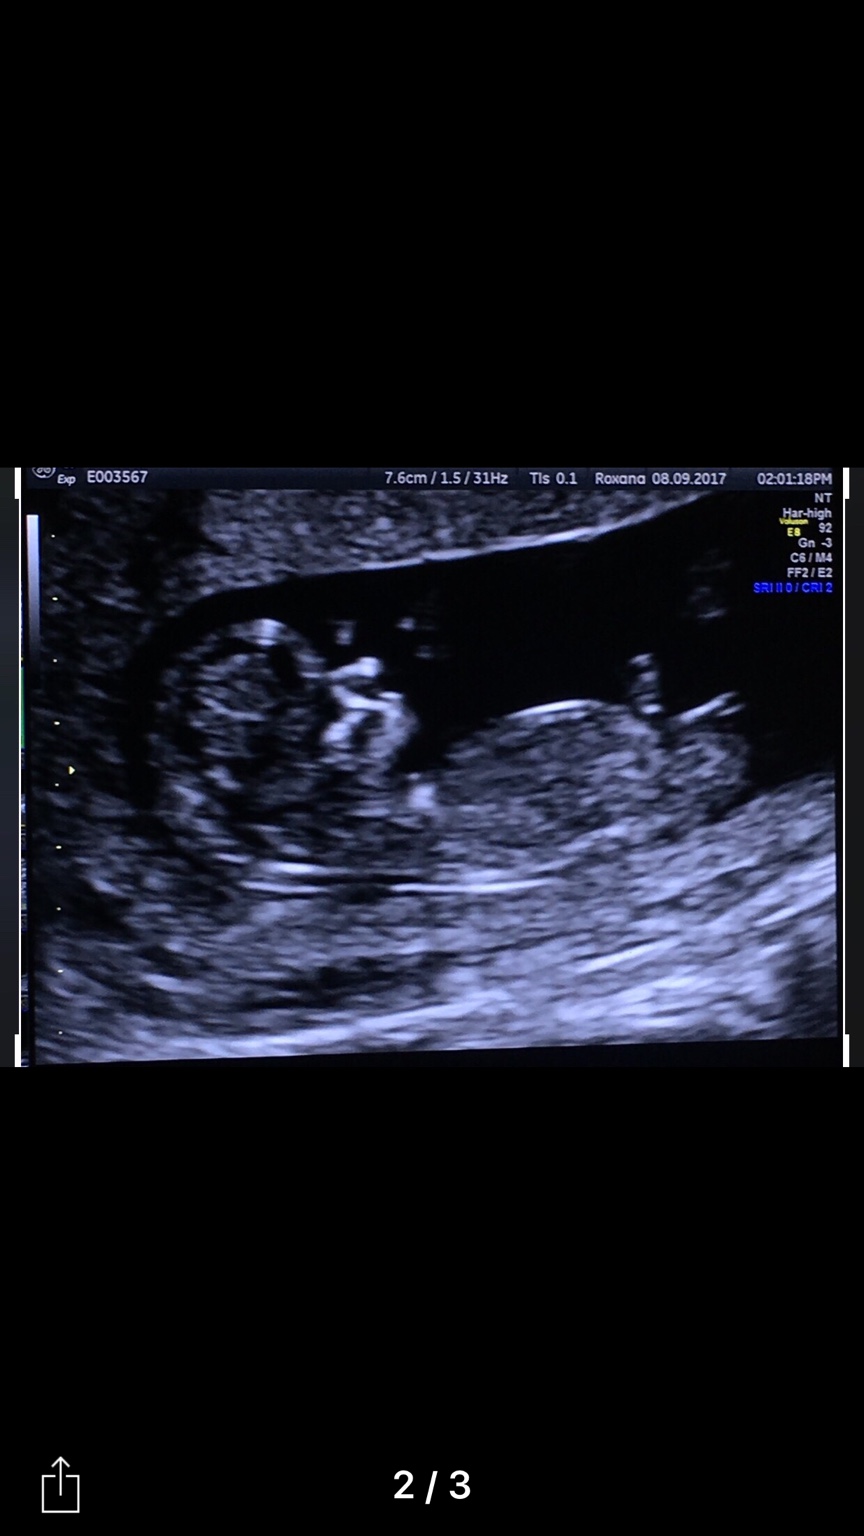

Ultrasound at 38 Weeks Pregnant 9 Months Pregnancy Growth Scan YouTube Why Is My Baby Measuring Small At 38 Weeks Causes of fetal growth restriction. Measuring small for gestational age means your fundal height is more than 3 centimeters smaller than expected for your stage of pregnancy. A common cause is a problem with the placenta. Fgr has many possible causes. Small for gestational age is a term used to describe a baby who is smaller than the usual amount. Why Is My Baby Measuring Small At 38 Weeks.